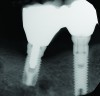

Fig 1 through Fig 6. Periapical radiographs of a 52-year-old man who received a fixed porcelain-fused-to-metal reconstruction supported by abutments attached to externally hexed dental implants. Fig 1 through Fig 3 are at initial prosthesis placement: maxillary right (Fig 1), textured surfaced threaded titanium implants at site Nos. 2, 4, and 6; maxillary anterior (Fig 2), implants at site Nos. 7 through 9; maxillary left (Fig 3), implants at site Nos. 12 and 14. Fig 4 through Fig 6 are 10 years post-insertion of the prosthesis: maxillary right (Fig 4), maxillary anterior (Fig 5), and maxillary left (Fig 6). Note minimal to no bone loss radiographically around the implants 10 years post-insertion of prosthesis.

During the first year after implantation, patients with completely restored edentulous ridges demonstrated a mean total bone loss ranging from 0.90 mm to 1.64 mm.58-60 After the first year, the mean annual rate of bone resorption ranged from 0 mm to 0.15 mm58-65 (Figure 1 through Figure 14).

Accordingly, if an increased rate of bone loss was selected to represent the pace of osseous resorption under dentures, a comparison between the rates of bone loss under dentures and around implants would indicate that implants preserve bone. Furthermore, the preponderance of data document that usually the amount of bone reduction per year around implants, in the absence of peri-implantitis, is so small that it has a negligible effect on the survival of implants, and it would take years to manifest noticeable bone loss and recession. For example, in areas under implant-supported prostheses (Figure 15), the ridge does not routinely manifest bone resorption and recession.66,67 However, there are patients who demonstrate different degrees of bone loss, and the reason for this is unknown.